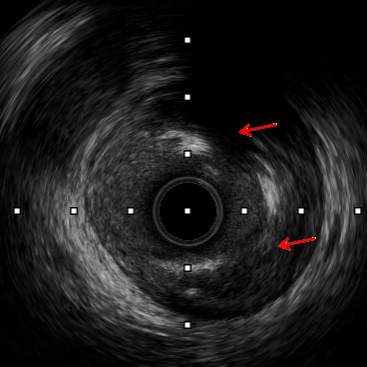

术中IVUS检查提示患者左回旋支近远段多处偏心钙化及钙化小结,钙化较重,导致多种介入器械难以通过,因此启动Shockwave冲击波球囊技术方案。

超过180度钙化环

钙化结节

钙化环断裂